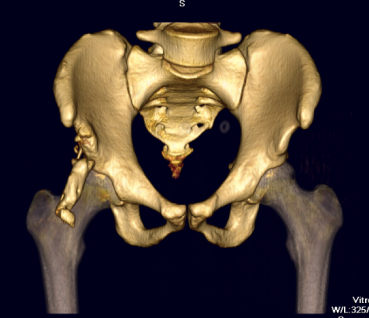

ASIS CT 1ASIS CT 2ASIS CT 3